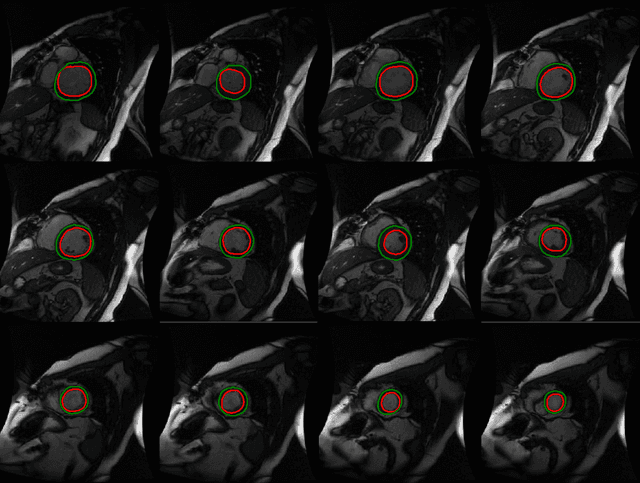

Abstract:Automated cardiac segmentation from magnetic resonance imaging datasets is an essential step in the timely diagnosis and management of cardiac pathologies. We propose to tackle the problem of automated left and right ventricle segmentation through the application of a deep fully convolutional neural network architecture. Our model is efficiently trained end-to-end in a single learning stage from whole-image inputs and ground truths to make inference at every pixel. To our knowledge, this is the first application of a fully convolutional neural network architecture for pixel-wise labeling in cardiac magnetic resonance imaging. Numerical experiments demonstrate that our model is robust to outperform previous fully automated methods across multiple evaluation measures on a range of cardiac datasets. Moreover, our model is fast and can leverage commodity compute resources such as the graphics processing unit to enable state-of-the-art cardiac segmentation at massive scales. The models and code are available at https://github.com/vuptran/cardiac-segmentation